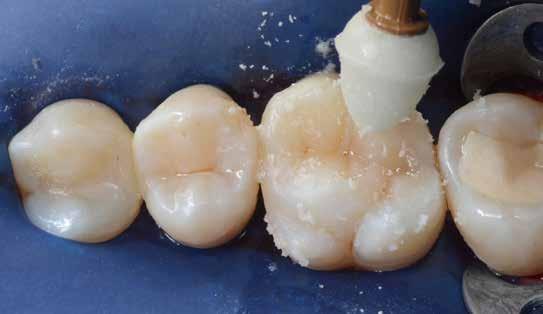

A posterior fogak direkt kompozit restaurációja az egyik leggyakrabban végzett beavatkozás a fogászatban. Az elmúlt években kiemelt figyelem irányult az elérhető eredmények optimalizálására, különös tekintettel a II. osztályú kavitás dobozának (Class II box) kialakítására, és a polimerizációs zsugorodásból eredő feszültség kezelésére. A téma körüli széles körű szakmai diskurzus ellenére van egy olyan lépés, amely gyakran nem kapja meg a kellő figyelmet: a mechanikai formázás protokollja. A mechanikai formázás alatt a restauráció kontúrjának kialakítását, a felesleges kompozit eltávolítását értjük a marginális szélekről, illetve ide tartozik a végső polírozás is. Ez a folyamat három fő lépésre bontható: a felszín oxigén által gátolt, nem polimerizált rétegének eltávolítása, a durva finírozás és a végső polírozás. Jelen publikációban részletesen bemutatjuk ezeket a lépéseket, valamint egy klinikailag hatékony megközelítést vázolunk fel a direkt posterior kompozit restaurációk befejezésére.

A durva finírozás 5 fázisa

A durva finírozás menete az alábbi 5 fázisban történik:

1. fázis

Egy durva szemcsés, közepes méretű (1/2 inch) alumínium-oxid finírozó koronggal (pl. FlexiDisc®, Cosmedent (https://www.cosmedent.com/product-category/finishingand-polishing/flexidisc/) a mesiális és distális marginális gerincek, valamint a csücsöklejtők kerülnek megmunkálásra, kb. 45°-os szögben a fog hosszanti tengelyéhez képest (lásd 1. ábra)

A korongot 5000–15 000 fordulat/perc fordulatszámon kell használni, vízhűtéssel vagy anélkül. A szerző a vízpermet nélküli alacsonyabb fordulatszámot részesíti előnyben, mivel így kedvezőbb a rálátás és precízebb munka végezhető.

A formázás rövid, szakaszos mozdulatokban történik, hogy elkerülhető legyen a zománc-kompozit határ túlmelegedése. Az asszisztens minden egyes szakasz után bőséges levegő-víz spray-vel (puszter) leöblíti a munkaterületet, ezzel javítva a rálátást és hűtve a restaurációt.

A finírozásnak mindig a kompozittól a fogszövet felé kell irányulnia, így csökkenthető a marginális rések és hibák kialakulásának kockázata [6].

Ennek a fázisnak kettős célja van:

1. A mesiális és distális marginális gerincek lekerekítése, ami esztétikailag kedvezőbb, elősegíti az interdentális tisztítást (a fogselyem beakadásának veszélye nélkül), valamint lehetővé teszi az ideálisabb okklúziós felszín kialakítását (mivel így helyet biztosít az antagonista fog csücskének).

2. A marginális kompozitfelesleg eltávolításával 90°-os záródás alakítható ki a fogszövet és a kompozit között. Ennek kialakítása azért javasolt, mert mechanikailag ez a legkedvezőbb találkozási forma. Amennyiben a felesleges anyag ottmarad, és a páciens ráharap, az rövid időn belül letörik, marginális hibát hagyva maga után.

Ezt követően a folyamatot közepes szemcseméretű koronggal kell megismételni, a marginális átmenet egységesebbé tételére. A korongot hátrafelé vezetve, enyhén meghajlítva alkalmazzuk. Ez a módszer – szemben az előrefelé történő vezetés technikájával – lágyabb, kerekebb, természetesebb profilt eredményez, míg az előrefelé történő használat inkább mesterséges hatású, lapos felületeket hoz létre.

Klinikai példa az alábbi képen látható:

2. fázis

2. ábra: A páciens egy nem megfelelő I. osztályú ezüstamalgám töméssel és II. osztályú szuvasodással jelentkezett. A fog izolálása kofferdám alkalmazásával történt.

3. ábra: A preparálás, a bondozás és a kompozit felvitele után. (Megjegyzés: némi kompozit túlfolyás látható a mesiális doboz axiális falain).

4. ábra: A durva finírozás után a restauráció pereme sima és anatómiailag is megfelelő.